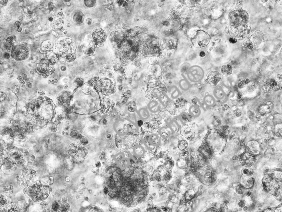

2.提升移植区血管化水平:将 hiPSC-CMs 与 RADA16 共注射到大鼠左心室壁,7 天后免疫荧光染色显示,移植区 CD31 阳性血管面积占比显著高于单独注射细胞组,且新生血管能与宿主血管功能性吻合(通过冠状动脉输注 GSL I lectin 验证),为细胞提供充足氧和营养;

大鼠左心室(LV)壁注射人类iPSC衍生心肌细胞(hiPSC-CMs)的移植、血管化和宿主血管吻合。

注射后7天零3个月注射到大鼠左心室(LV)壁的hiPSC-CMs的肉瘤组织和血管化